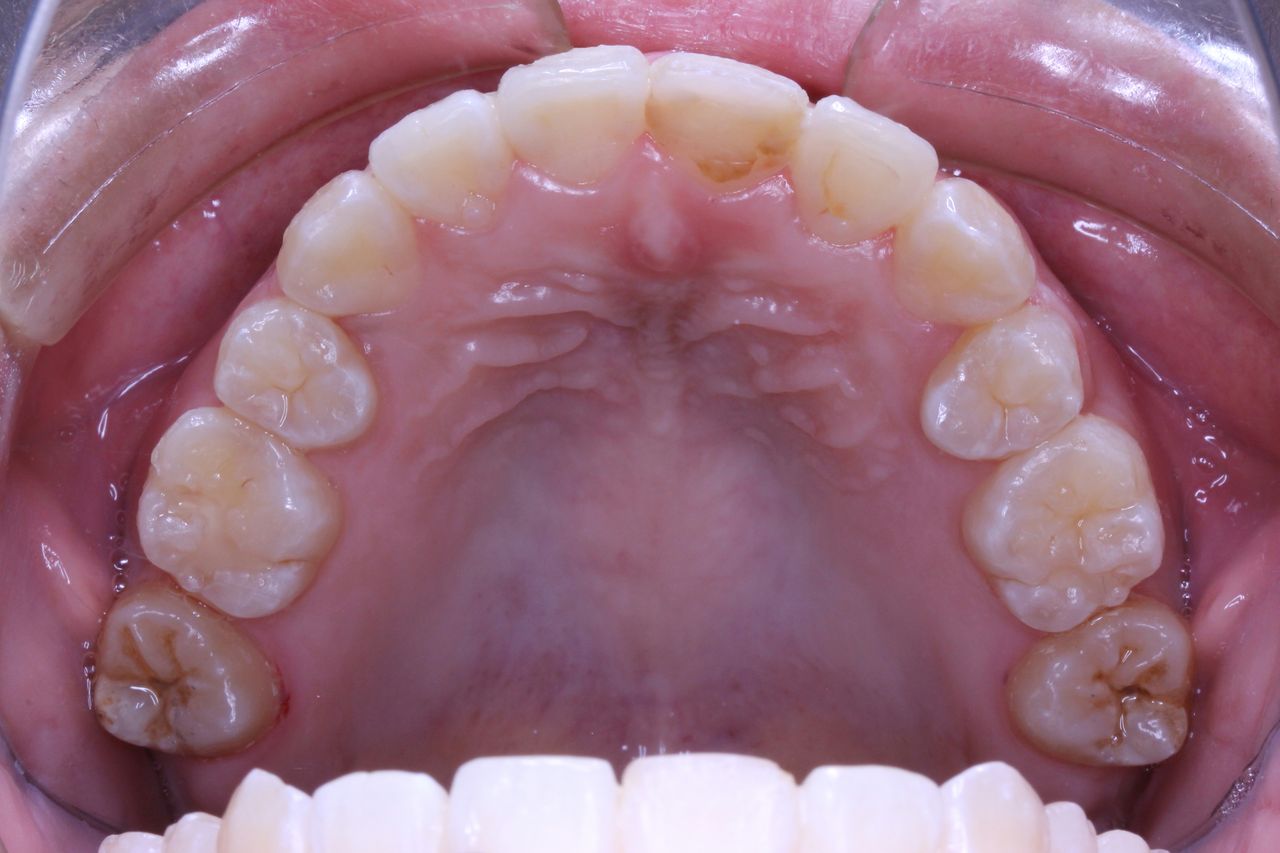

上方向からみると奥歯が頬方向に傾いております。

上の奥歯の部分を注目してください。親知らずの前の歯が2本抜歯してるのがわかると思います。

つまり、この時点で上顎だけで3本も抜歯してます。そういう意味では患者さんは不安になりますかね(笑)